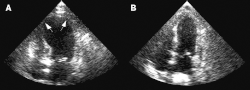

![]() Схематическое изображение кардиомиопатии такоцубо (A) в сравнении с нормой (B). | |

В ходе наблюдения за пациентами часто отмечается выбухание верхушки левого желудочка с гиперкинезом его основания. Картина выбухания верхушки сердца, сочетающегося с сохранённой функцией его основания, дала синдрому японское название тако цубо («ловушка осьминога»)[5].